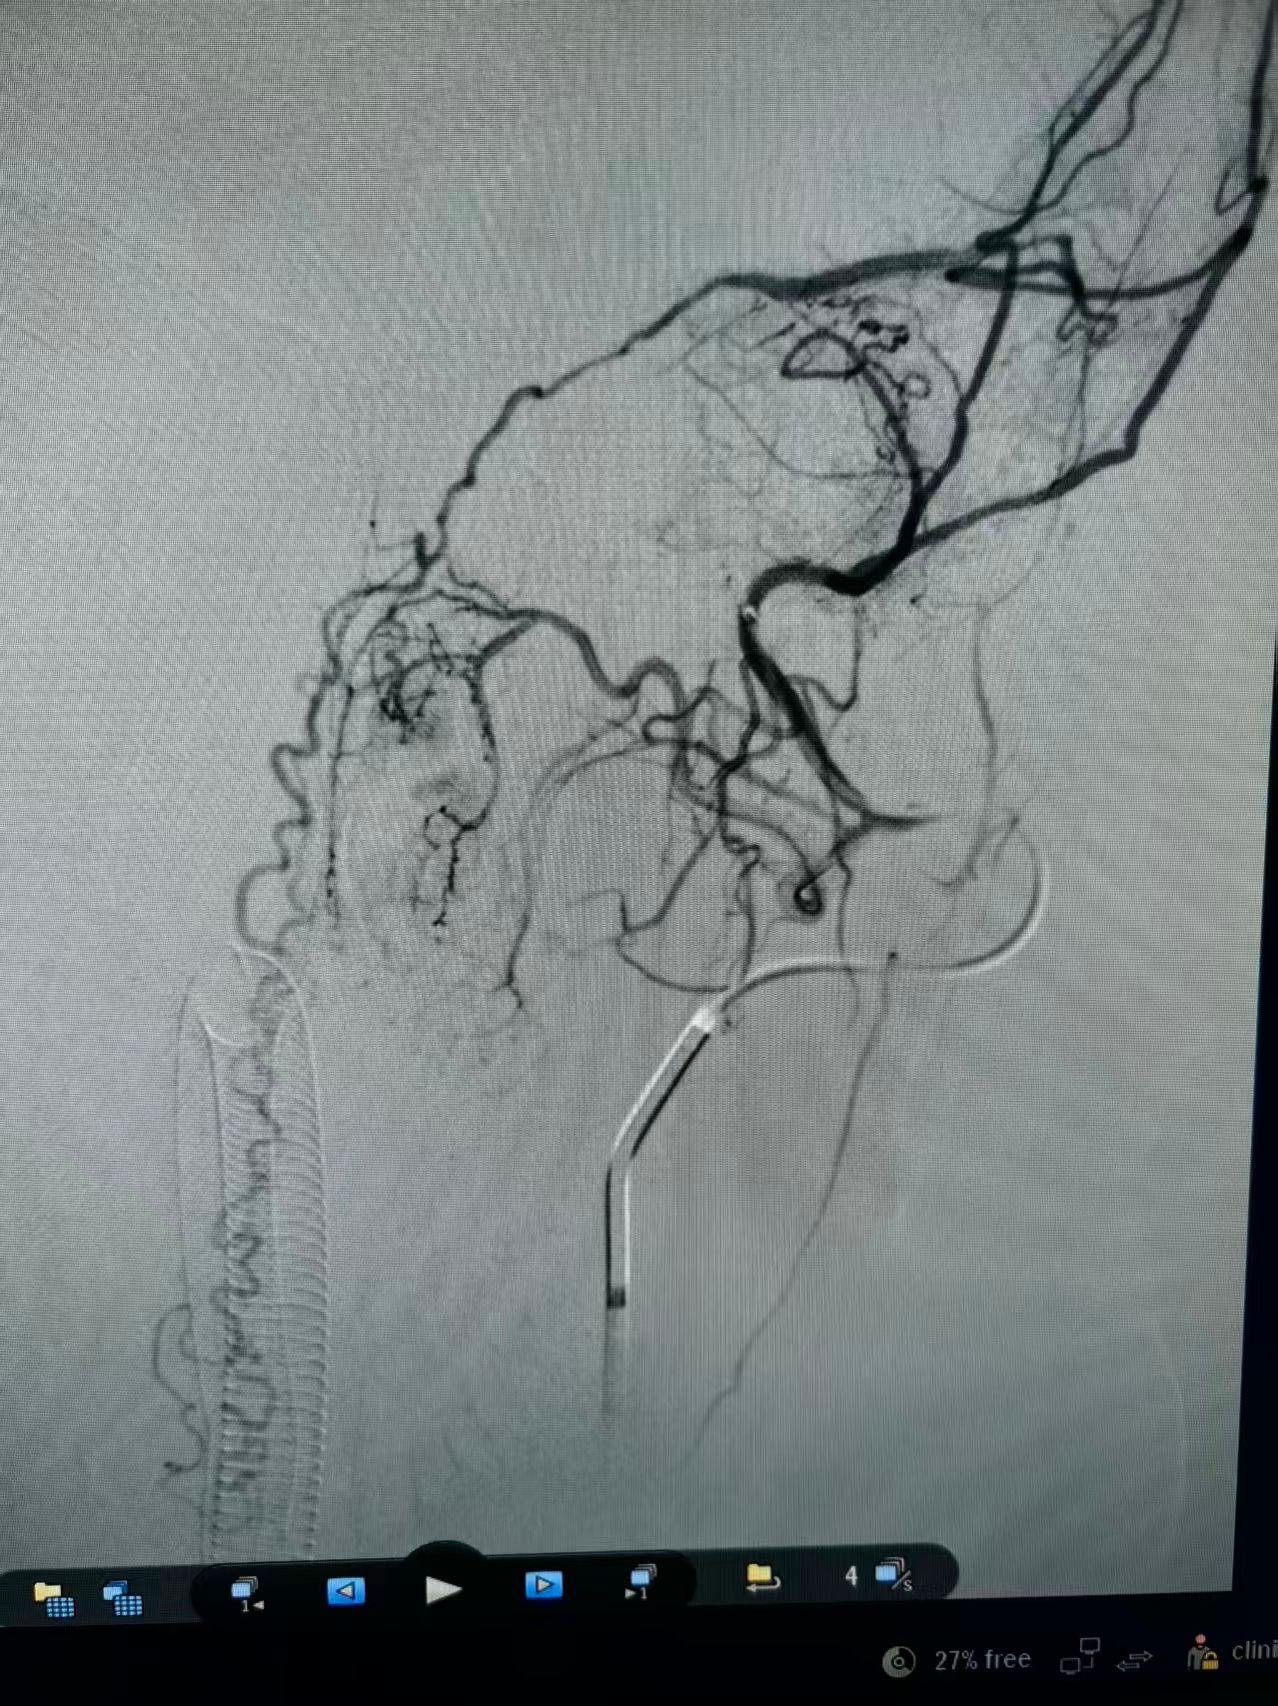

团队结合患者病史、影像学检查以及使用激素后加重的特征,讨论后认为动静脉瘘的可能性较大。但全脊髓造影并未发现硬脊膜动静脉瘘,那么,这个瘘会不会在颅内,只是朝脊髓引流了。根据这个猜测,许刚副主任医师团队为患者进行了全脑血管造影,初步的血管造影并未发现明显病灶。团队并未轻易放弃,又对可疑的各分支血管进行了超选择性造影。最终发现了该患者为脑膜中动脉及枕动脉脑膜支供血的一个非常细小的瘘口。该瘘位于岩骨脊,向下朝脊髓引流,不仔细研究很可能发现不了。

明确诊断后,许刚副主任医师、僧志远主治医师运用介入技术成功对该瘘口进行了栓塞,栓塞术后次日患者的双侧下肢感觉及运动功能就明显好转。一周后患者转当地医院继续康复治疗。

术前脑膜中超选正位